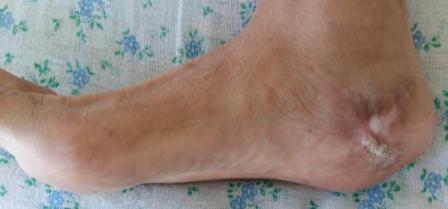

Вчера госпитализирован пациент 1970г.р., в ноябре 2014г, получил

о/перелом пяточной кости. в другой клинике произведена КДО аппаратом

Илизарова, после трех месяцев аппарат сняли, и больной начал наступать и

ходить, все это со слов больного (р-снимков нет.). Жалобы боль при

ходьбе, которая в динамике усиливается, об-но: деформация пяточной

кости, движение в г/стопном суставе почти в полном объеме, по медиальной

поверхности пятки рубец, плотно спаянный с костью.